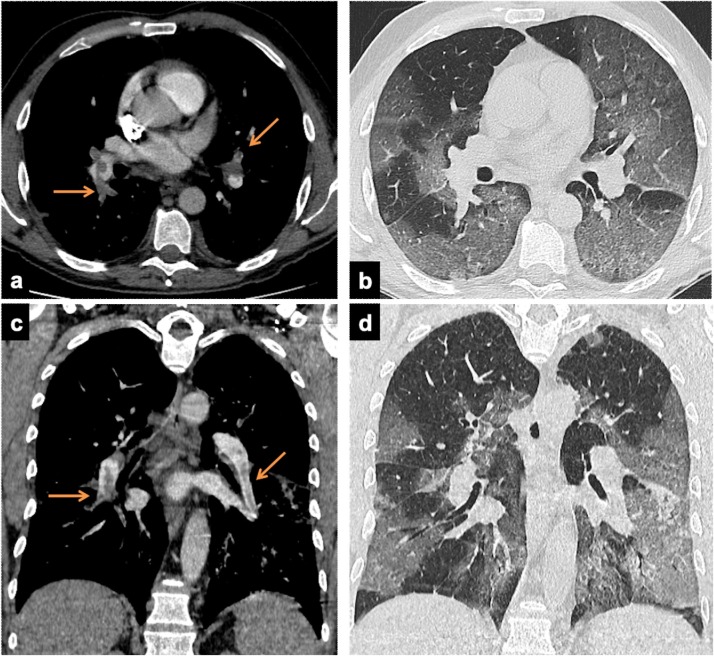

The clinical PE suspicion relayed on a sudden worsening breathing status during the hospitalization (91 patients, 79.9 %) or on ER arrival (23 patients, 20.1 %). CTA revealed PE in 65/114 patients (57 %): arteries of one pulmonary lobe in 40 %, ubiquitous in 18.5 %, main trunk and/or main pulmonary arteries in 11 cases (16.9 %) (Fig. 1 ). The lobes where most frequently PE occurred were the right lower (49, 75.3 %), the left (37, 56.9 %) and the right upper (31, 47.7 %).

Fig. 1.

Axial (a and c) and paracoronal (b and d) CT images in two 56 years old males, with d-dimer levels of 13.16 ug/mL and 4.99 ug/mL respectively. CTA demonstrate thromboembolic defects involving the pulmonary trunk and main arteries (arrows, a and b). The lung window demonstrates bilateral patchy consolidations and GGO (progressive stage).